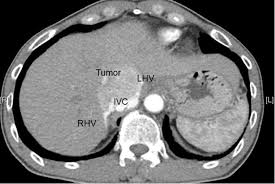

Hepatocellular Carcinoma Nature Reviews Disease Primers